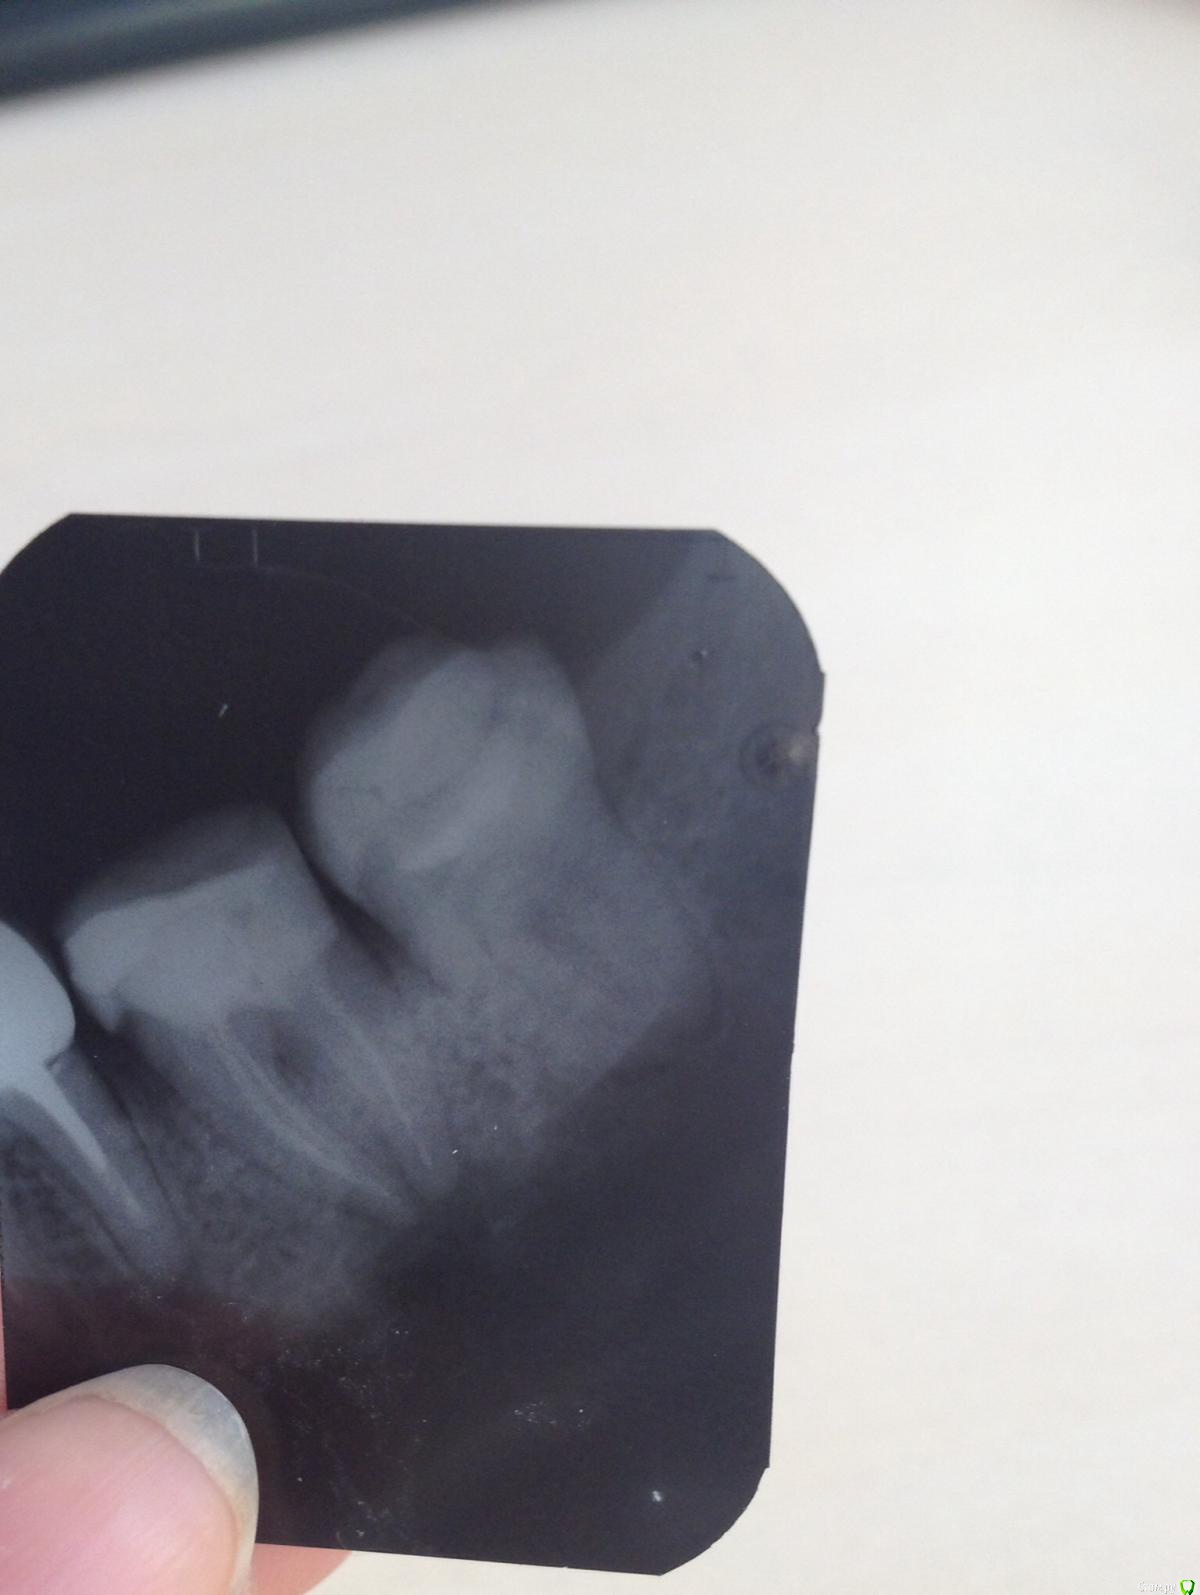

Тасечка Опубликовано 6 мая, 2015 Поделиться Опубликовано 6 мая, 2015 Добрый день! Сильная боль и днем и ночью с 3 мая,кеторол на второй день перестал помогать,пью и его и нурофен,облегчение на час.зуб 7-ка,нервы удалены давно,откололась пломба и в марте запломбировала.сейчас стал жутко болеть,пошла в госполиклинику,врач глядя на снимок,сказала воспаление(под корнями на снимке вроде как затемненено) и ничего сделать не может в таком случае-только к хирургу или в платную попробывать.обратилась в частную,предложено было распломбировать,положить лекарство на два месяца и затем заново пломбировать.цена -8 тыс.,для меня это очень дорого.Пошла сегодня к другому врачу в госполиклинике.Врач обратила внимание на карманы с зубом,продувая-идет запах и что воспаление и боль может из за этих карманов,назначила физио-ультразвук на 5дней,промыла карманы,уколола левомицин и поставила лечебную пасту на час.Завтра снова на укол и промывание.Врачу верю,но смущает такая ужасная боль,которая не поддается таблетках.Такая боль возможна из-за карманов?может надо было все таки распломбировывать,как вы считаете?Не знаю как дожить до завтрашнего укола и промывания,силы терпеть боль почти не осталось.Ответьте,пож-та,что думаете? Ссылка на комментарий

Гарриевич Опубликовано 6 мая, 2015 Поделиться Опубликовано 6 мая, 2015 У Вас периодонтит 7 и 6 зуба (на снимке виден только один его корень, задний)Промывание и уколы лечением не являютсяНужно распломбировывать корневые каналы 7 зуба, закладывать лекарство и заново пломбировать корневые каналы зуба. Далее зуб обязательно нужно закрыть герметичной реставрациейС 6 зубом такая же история Ссылка на комментарий

red_butler Опубликовано 6 мая, 2015 Поделиться Опубликовано 6 мая, 2015 нужно исключить пульпит в зубе мудрости, если подтвердится - удалить 1 Ссылка на комментарий